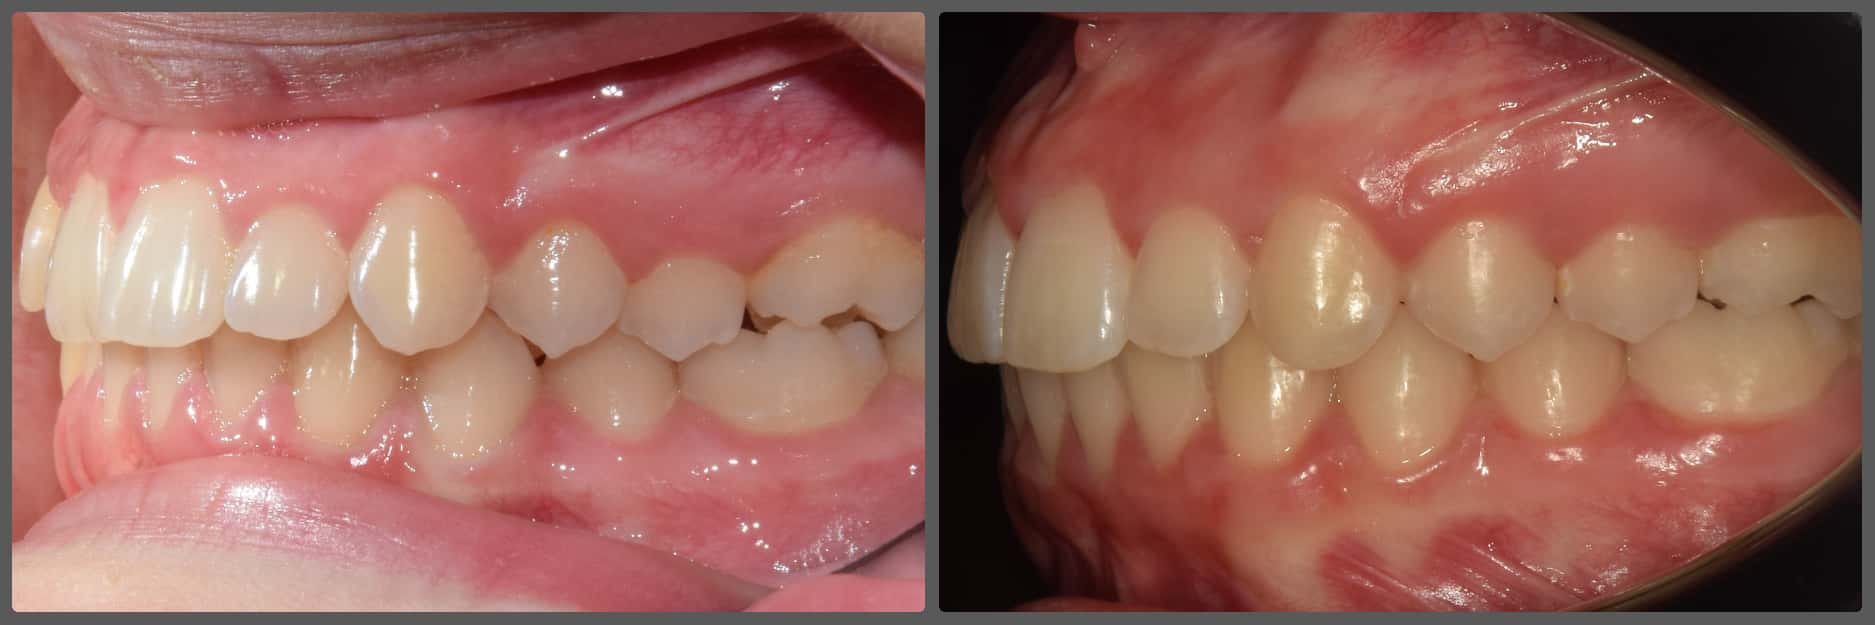

Bálint a 90 fokban elfordult jobb felső kismetszője miatt keresett meg engem. A vizsgálatokat követően kiderült, hogy a probléma ennél jóval komplexebb: súlyos keresztharapást, súlyos mélyharapást és felső rágósík billenést diagnosztizáltam nála. Alsó-felső H4 önligírozó fogszabályozó készülék, intermaxilláris gumihúzás és elülső harapásemelők segítségével korrigáltuk az eltéréseket. A bal oldali rágósík billenést fogszabályzási miniimplantátum alkalmazásával oldottuk meg. A bal felső-elülső fogakat felfelé mozgattuk, a miniimplantátumhoz húzva. Bálint esete igen komplex volt, ám kiváló együttműködésének köszönhetően 26 hónap alatt végeztünk a kezelésével (beleértve a 2-3 hónapos COVID-19 miatti leállást is). Az eredmény úgy gondolom magáért beszél!